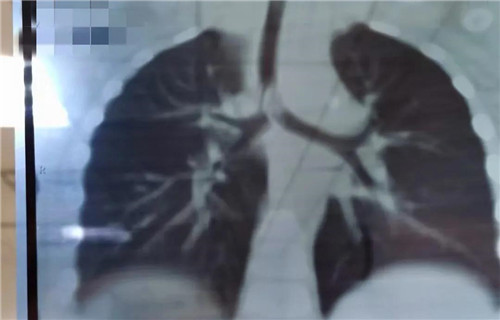

22日晚,19个月女宝诺诺(化名)在家吃花生突然呛咳,爸爸把她倒过来拍几下,诺诺吐出半个花生,但没好转,又出现喘憋,情况非常紧急......夫妻俩立即带孩子来到a片网站 就诊,耳鼻喉科夜班医生接诊。医生初步判断是气管异物,而且很可能在主气道。肺CT三维重建显示,异物正堵在主支气管与分叉气管交接口,基本堵满了,诺诺出现吸气性呼吸困难。情况紧急,考虑急诊手术取出。当晚9点多,诺诺住院。此时,耳鼻喉科主任沙颖、副主任李莉萍、刚加完班回家的李萍大夫,麻醉科主任王丽波也正在从家往医院赶。

当晚12点,诺诺进入手术室。因为异物占据气道,孩子又小,取异物一定要快。支气管镜进入后显示,半个完整花生堵在主支气管分叉位置,堵塞面积达到4/5以上,仅在花生边缘与气管之间留有少许通气的地方。花生已经被浸泡得很软了,异物钳夹过程中,不能完整夹持,抓出来的都是或大或小的碎块。随着一块一块碎花生被取出,诺诺的呼吸渐渐地好了起来。诺诺被推回病房时,已经快凌晨2点了。